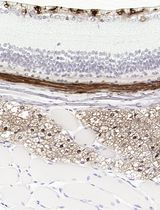

These paraffin-embedded organoid slides can subsequently be utilized for staining in the same way as conventional tissue slides, depending on the research purpose. Here, H&E and IHC were performed as representative examples, focusing on diagnostic markers such as CK19, Pan-CK, Ki-67, P63, and P53 (Figure 5).

Figure 5. Histological and immunofluorescence characterization of formalin-fixed paraffin-embedded (FFPE) organoids. Representative images show brightfield morphology of patient-derived organoids (DIC) prior to fixation, hematoxylin and eosin (H&E), and immunohistochemistry (IHC) staining for cancer diagnostic markers, including CK19, Pan-CK, Ki-67, P63, and P53. DIC images were acquired using a Zeiss microscope with ZEN 3.7 software. Stained slides were scanned using the Vectra PolarisTM Automated Quantitative Pathology Imaging System (Akoya Biosciences). The images were captured with the Phenochart software. PC, pancreatic cancer organoid established from surgical tissue; PCE, pancreatic cancer organoid established from endoscopic ultrasound–guided fine needle biopsy; PCG, pancreatic cancer organoid established from percutaneous liver gun biopsy; PCA, pancreatic cancer organoid established from ascites; CCG, cholangiocarcinoma organoid established from percutaneous liver biopsy; CC, cholangiocarcinoma organoid established from surgical tissue; OC, oral cancer organoid established from surgical tissue.